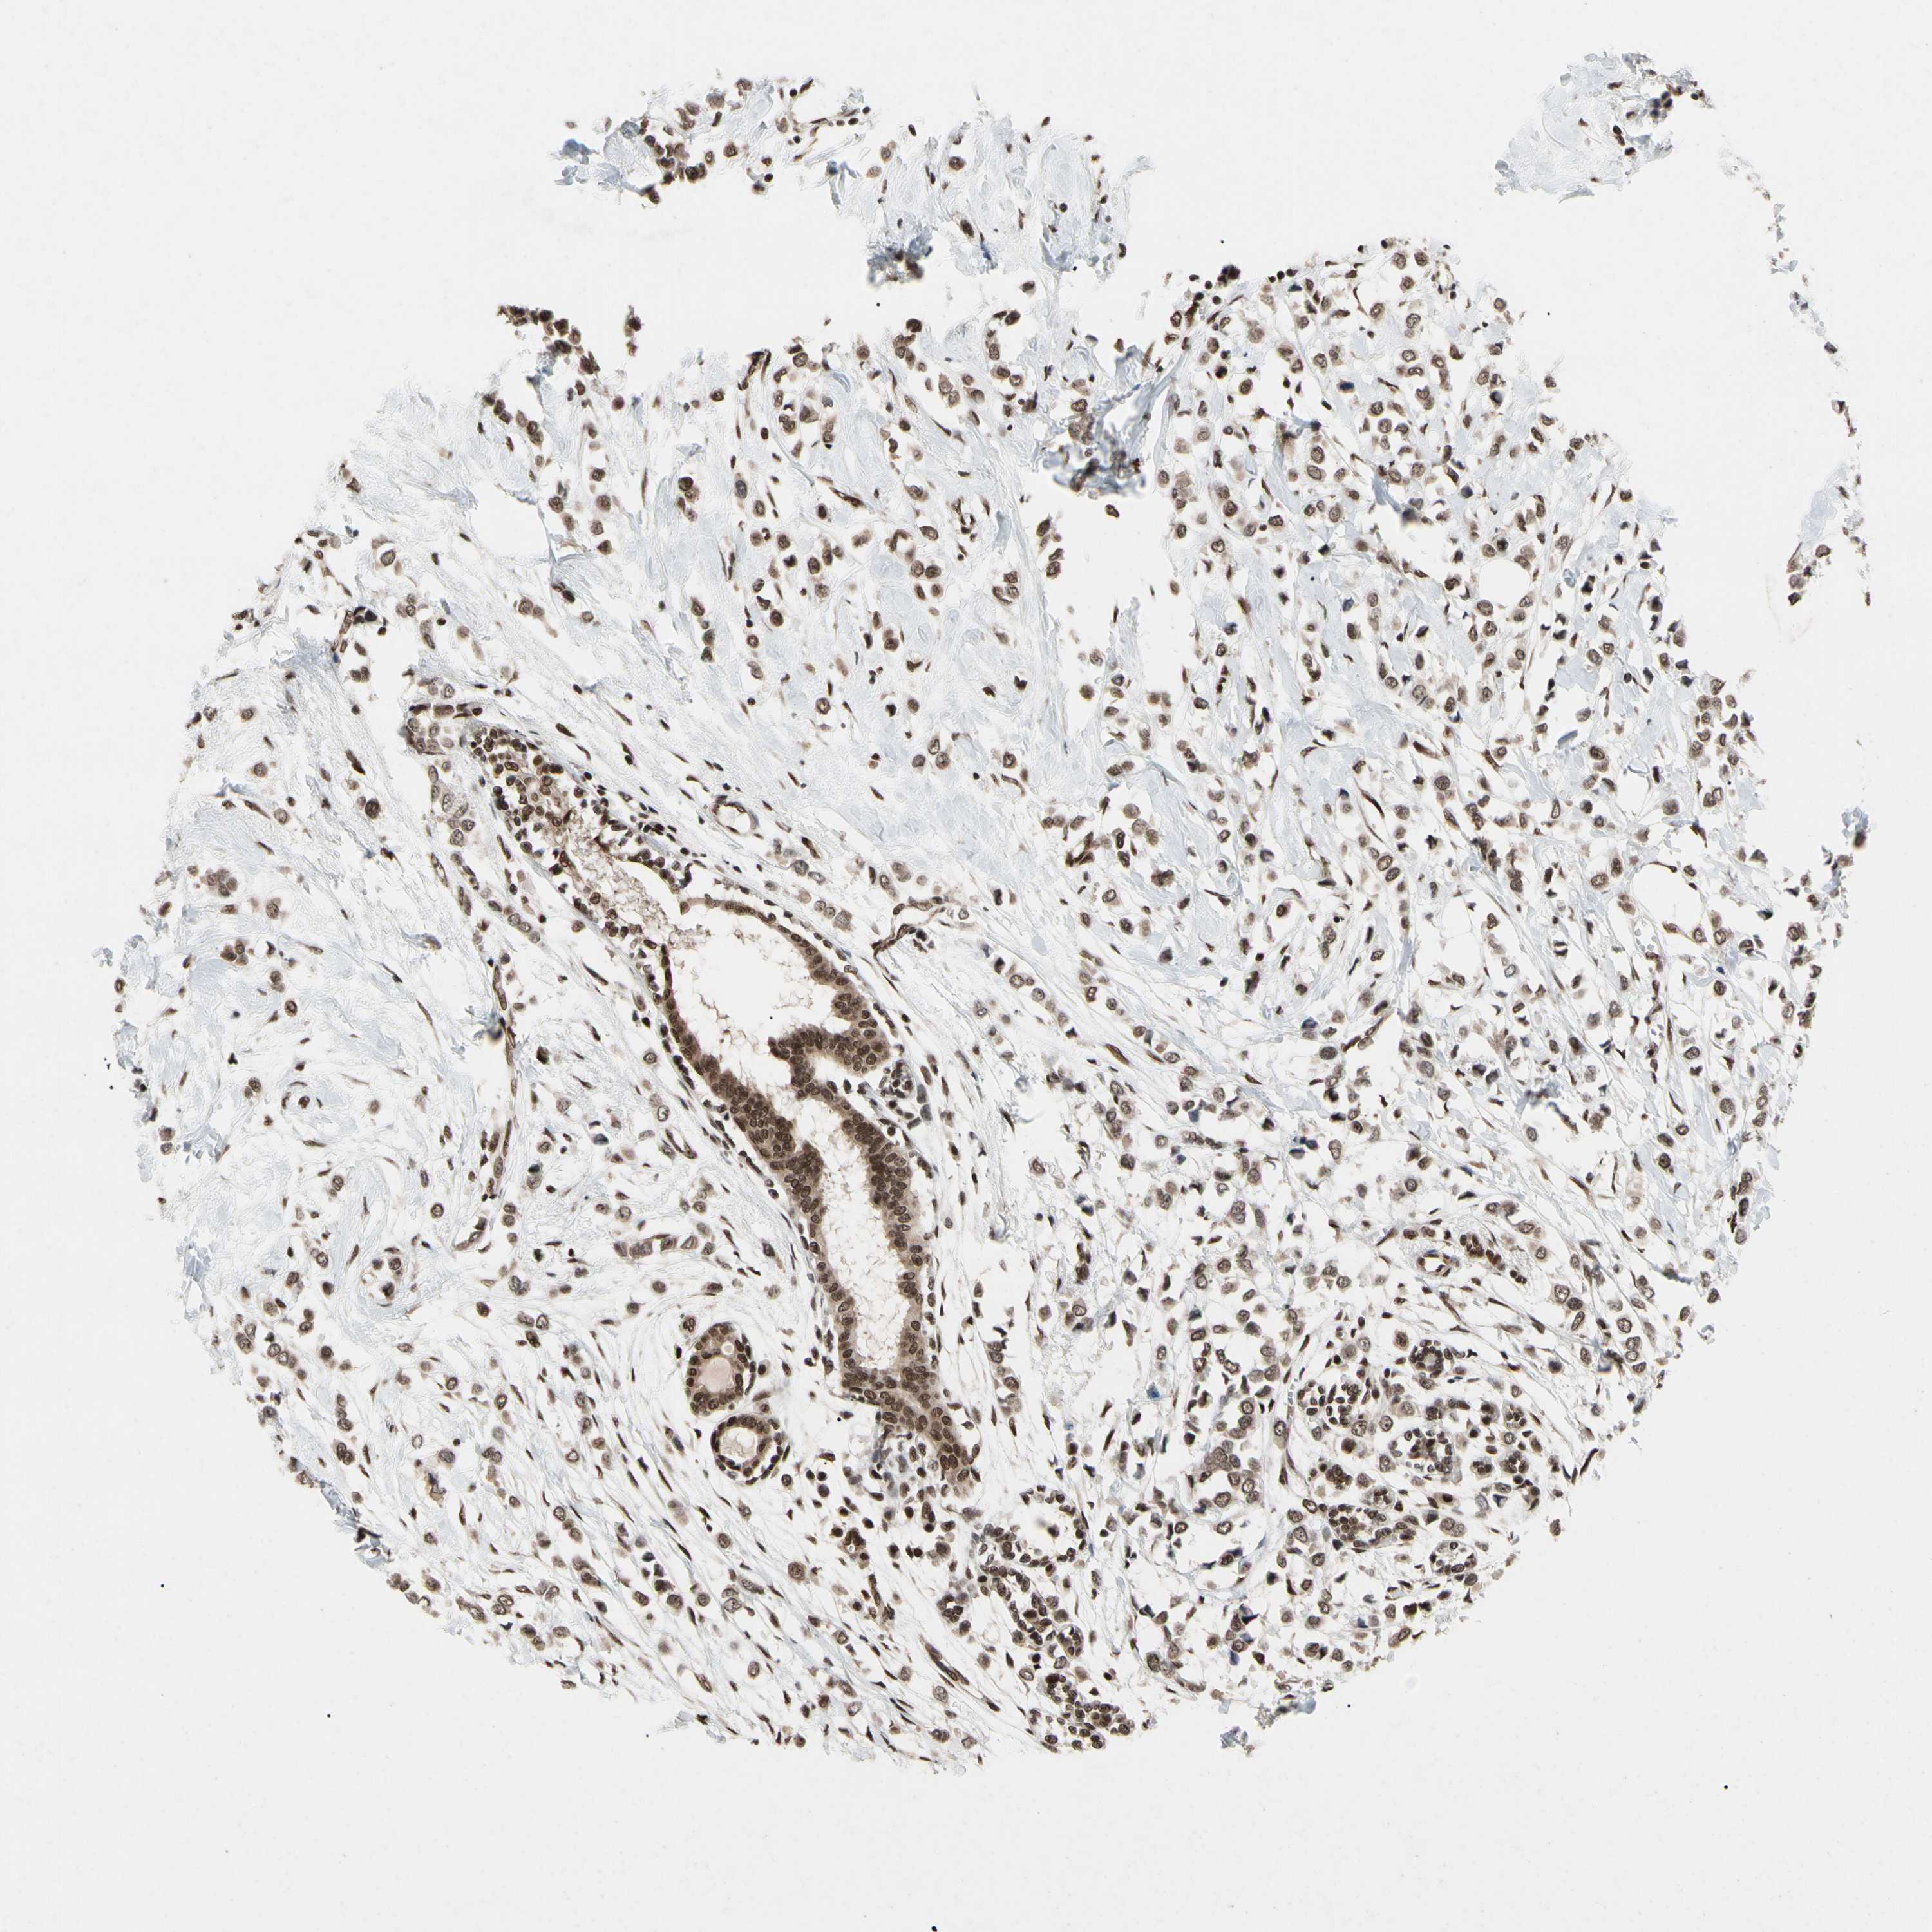

CANCER BREAST CANCER Show tissue menu

BRCA TCGA BRCA VALIDATION PROTEIN EXPRESSION

FAM98B is potential prognostic, high expression is unfavorable in Breast Invasive Carcinoma (TCGA)